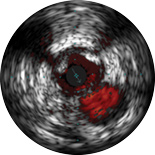

ChromaFlo provides easy assessment of stent apposition, lumen size and more by highlighting blood flow red at the touch of a button. ChromaFlo is available on Philips imaging systems.

Designed to make lumen size and stent apposition instantly recognizable and help identify branches, dissections, thrombus, and plaque distribution in bifurcations. ChromaFlo highlights blood flow red to identify:

No flushing and no special procedures are required during imaging. Simply activate ChromaFlo with a click.